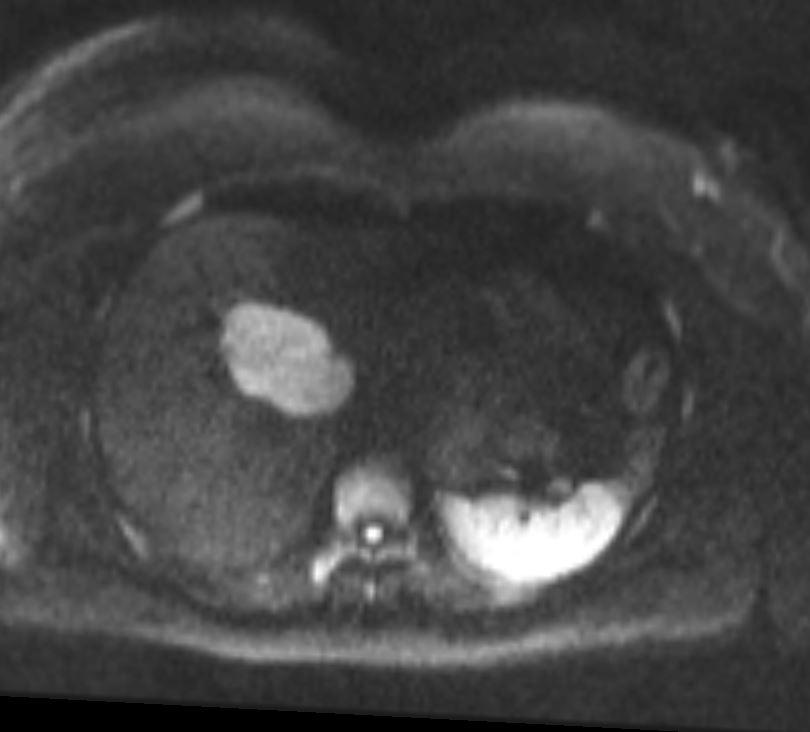

Case of the Week 28 2017 What is the most likely diagnosis? Answer Answer: Cavernous Liver Hemangioma Kategori:Cases Önceki yazı Case of the Week 25 2017 Sonraki yazı Case of the Week 29 2017